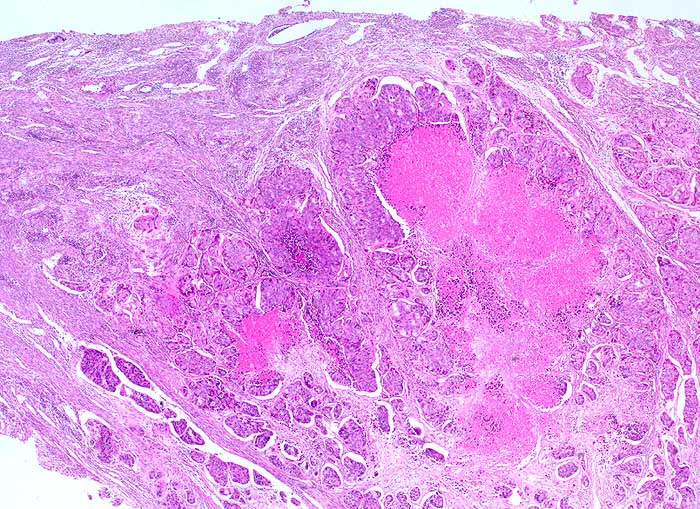

PathoPic ID 6397 - Kolonkarzinom: Metastase

Kolonkarzinom: Metastase

maligner Tumor

Portio

Genitalorgane, weiblich

Infiltrate eines soliden Adenokarzinoms mit ausgedehnten komedoartigen Nekrosen gut passend zu Metastasen eines Kolonkarzinoms. Gefässeinbrüche.

Kolonkarzinom. Postmenopausale Blutung.

Histologie

25